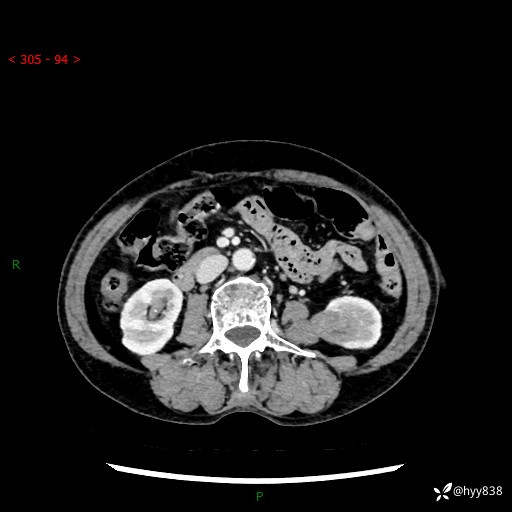

72岁/女,检查发现左肾占位1天。为了满足诊断,常规四期后,又加了延迟期-结果公布~

【患者信息】:72岁/女

【主诉】:检查发现左肾占位1天

【现病史及既往史】:患者于1天前检查发现左肾占位,无畏寒发热,无咳嗽咳痰,无腰腹部疼痛不适,无肉眼血尿、无尿频尿急症状,起病来,患者未行特殊治疗,为求进一步诊治,门诊以"左肾占位"收治入院。 发病来患者精神、饮食、睡眠良好,小便如上,大便正常,体重无明显变化。

【检查】:肾脏CT平扫+增强